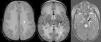

Transversal T2-weighted images showing extensive involvement of the periventricular, deep and cerebellar white matter (white asterisks). Involvement of the corpus callosum (black asterisks) and the corticospinal tract, from the posterior limb of the internal capsule and pyramidal tracts in the brainstem (black arrows). Abnormal signal intensity in the thalamus and medial lemniscus in the brainstem (white arrows). Trigeminal nerve trajectory involvement (white arrow head).

We present the cases of two female twins aged 14 months, born preterm at 32 weeks’ gestation to consanguineous parents, and referred for evaluation due to failure to thrive. They were followed up in the clinic, exhibiting mild psychomotor delay at age 9 months. At 14 months they were admitted for evaluation of severe malnutrition. The neurological assessment revealed psychomotor regression with absence of sitting and turning, irregular eye focusing and tracking, and little interest in objects. A metabolic and nutritional screening was performed, revealing a mild elevation of lactate in blood. The findings of brain and spinal cord MRI were compatible with severe, uniform diffuse involvement of the periventricular, centrum semiovale, and cerebellar peduncle white matter. There was involvement of the posterior and anterior regions of the corpus callosum, the corticospinal tracts from the posterior limb of the internal capsule through the brain stem to the lateral corticospinal tracts in the spinal cord and of the ascending tracts from the dorsal columns of the cervical spinal cord and medial lemniscus of the brain stem to the thalamus and corona radiata (Figs. 1 and 2). We performed a magnetic resonance spectroscopic imaging (MRSI) scan that revealed a decreased N-acetyl aspartate/creatine ratio and lactate elevation. The disease progressed slowly in both twins, with gradual neurological deterioration and recurrent respiratory infections leading to their death at age 2 years.